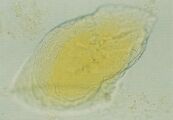

Р

ис. 59. Микрофотография слоистого кристалла в мочевом осадке собаки, описанной в рис. 49. Его появление свидетельствует об активном росте кристалла (не окрашено, увеличение Х 128).